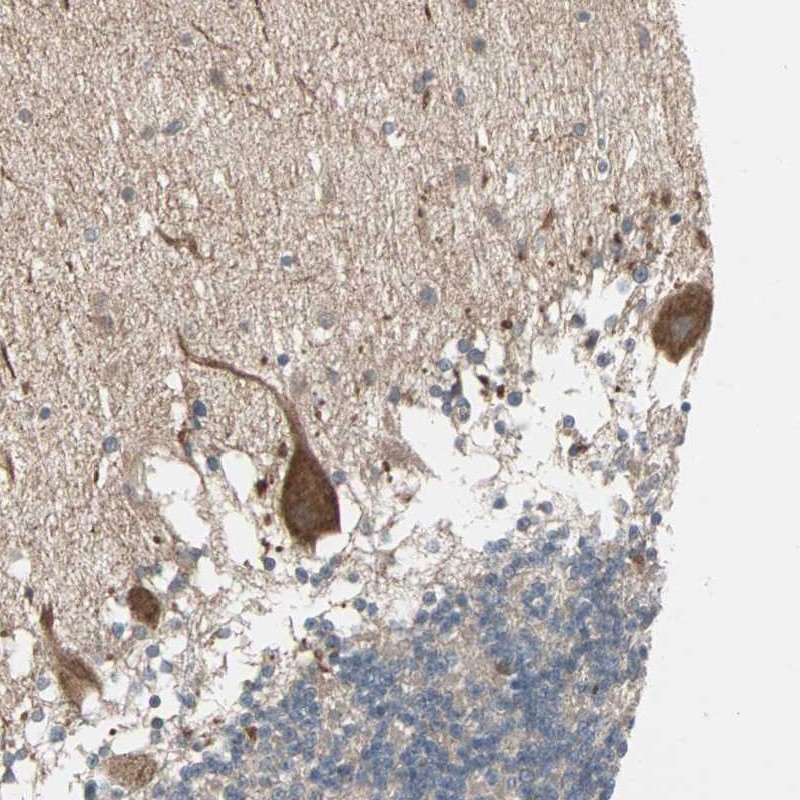

Immunohistochemical staining of human cerebellum shows strong cytoplasmic positivity in purkinje cells.